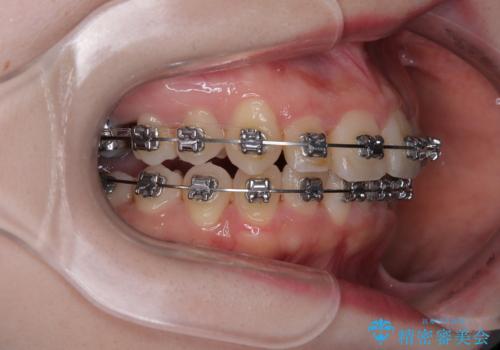

- メタルブラケット

- 1年11ヶ月

- 上下前歯のデコボコを気にして来院された患者様です。

マウスピースでもワイヤー装置でも対応可能でしたが、右側の咬み合わせが上顎がやや前方に位置していることから、補助装置を使用することが推奨されました。

自己管理の煩わしさを気にして、補助装置併用によるワイヤー装置での矯正治療を行うこととしました。

右上と左下の第一大臼歯2本が周辺の歯と比べて位置がずれていたため、ゴムかけやワイヤーに曲げを入れることで移動を試みましたが、どうよら癒着をしており、移動困難と判断されました。

見た目や咬み合わせに違和感がないとのことで、癒着歯の無理な移動は試みずに治療を終えることとしました。